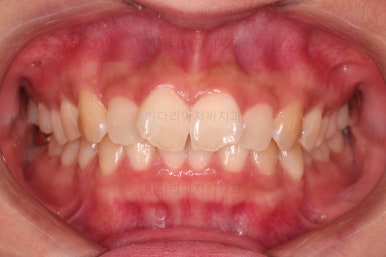

1. 초진

초진 시 입안의 모습입니다.

어금니 쪽은 약간 삐뚤긴 하지만 꼭 교정해야 할 정도는 아니고, 불편감 없이 비교적 잘 맞물리는 상태였습니다.

다만, 앞니ㅉㄱ이 공간이 부족해서 중간 치아들이 많이 회전되어있는데, 이를 환자분들의 표현에 따르면 "나비치아" 라고 부릅니다.

위아래 중간 앞니가 모두 나비치아처럼 되어있고요.

윗니가 아랫니보다 앞쪽으로 나와 있는 모습에 아래앞니가 윗니쪽으로 깊숙이 올라간 "과개교합" 양상을 보였습니다.